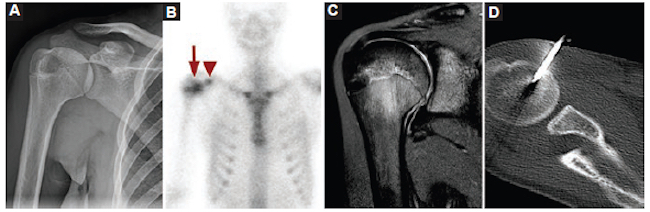

Mujer de 18 años con omalgia derecha postraumática de meses de evolución. En la Rx de hombro derecho se informó una dudosa imagen radiolúcida en el troquín, de características indeterminadas. En el centellograma óseo se observaron dos focos de hipercaptación, uno epifisario y otro en la apófisis coracoides. El informe de resonancia magnética (RM) sugirió una lesión traumática, pero no descartó otro origen. Ante la duda diagnóstica, se procedió a realizar una biopsia bajo TC (Fig. 2).

El resultado anatomopatológico informó cambios reparativos. La conclusión diagnóstica fue lesión por estrés.